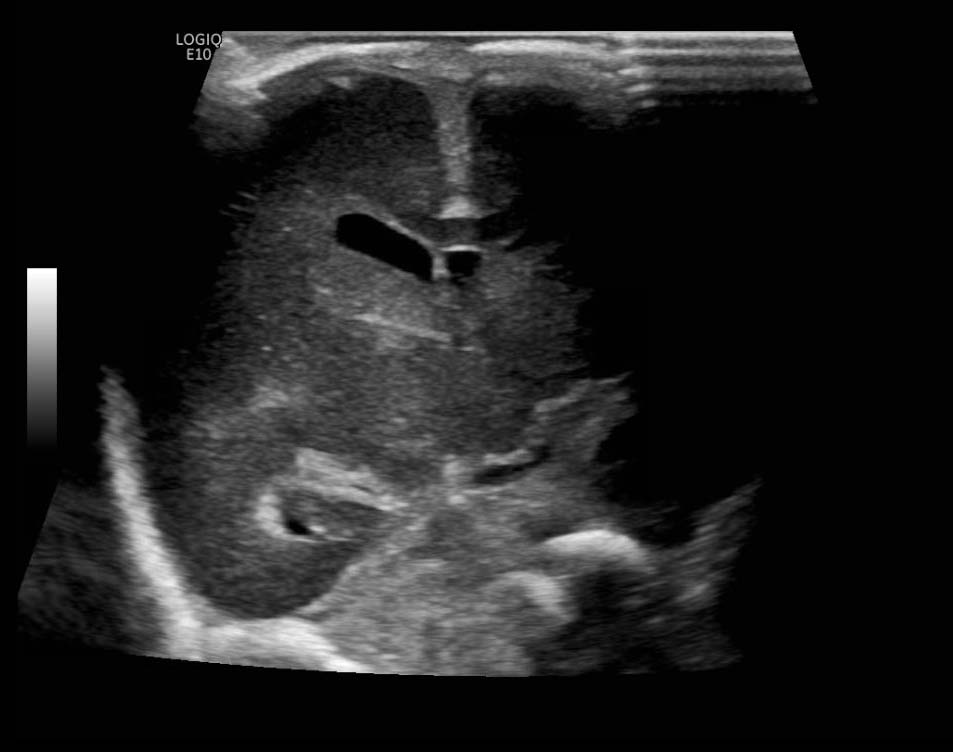

Age: 4 days (born at 24 weeks)

Sex: Male

Indication: Evaluate for germinal matrix hemorrhage

Grade 2 germinal matrix hemorrhage

Sample ReportLeft germinal matrix hemorrhage involving the caudothalamic groove and layering in the occipital horn of the left lateral ventricle without hydrocephalus (grade 2).

No abnormal brain parenchymal echogenicity or extra-axial collections.

Premature sulcation pattern.